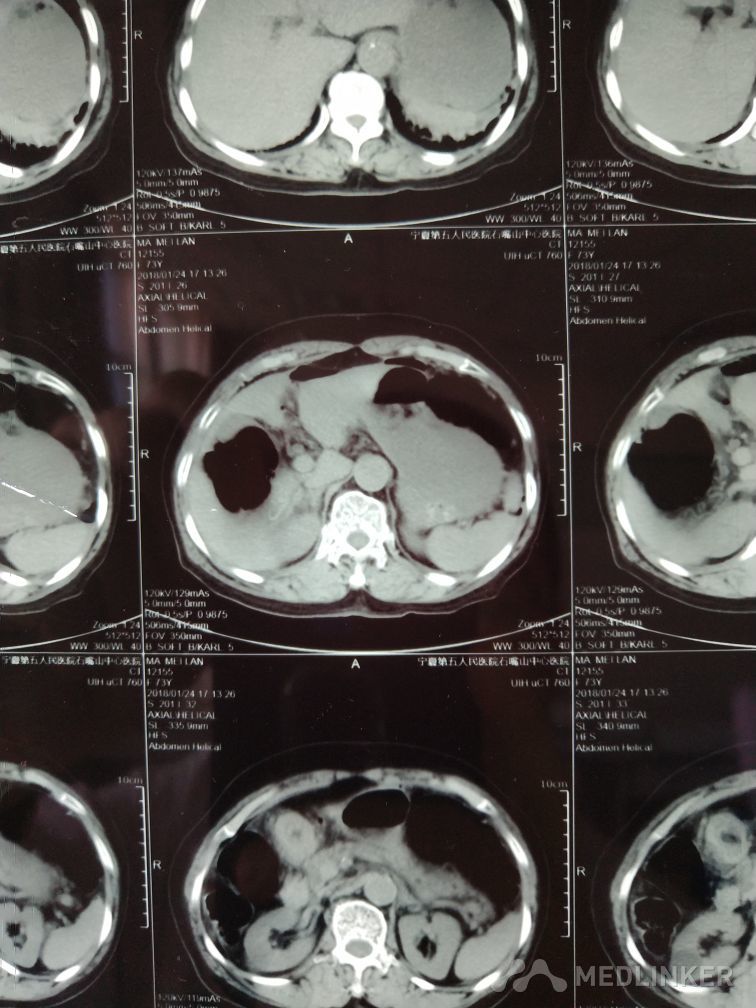

胃穿孔

胃穿孔修补术